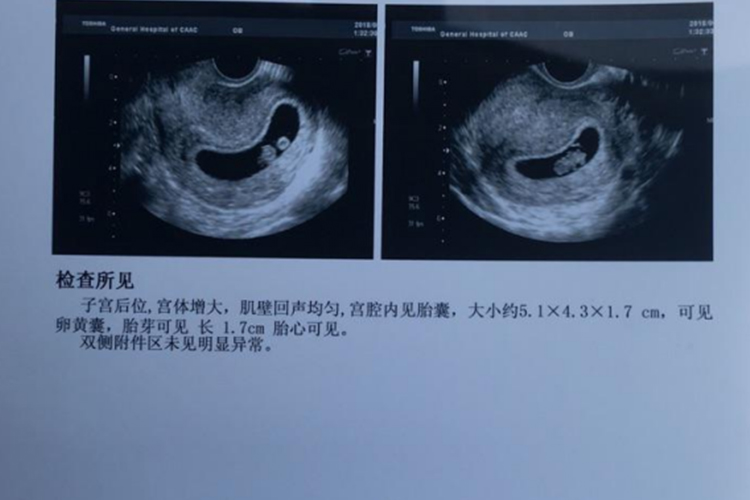

怀孕进行B超检测,B超单上会有关于子宫变化、宫腔内胚胎变化及子宫附件的描述,若B超单显示在宫腔内见妊娠囊或胎囊等组织,为正常宫内妊娠。

怀孕早期B超检查的主要目的是确定宫内妊娠,排除异位妊娠、滋养细胞疾病、盆腔肿块等。若为多胎,可通过胚囊数目和形态判断绒毛膜性。停经35日时,宫腔内见到圆形或椭圆形妊娠囊。

妊娠6周时,可见到胚芽和原始心管搏动,妊娠11-13周测量胎儿头臀长度能较准确地估计孕周,校正预产期。